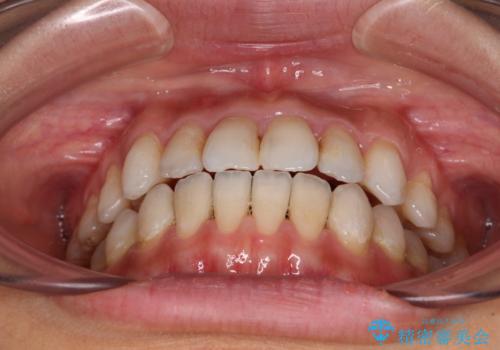

【モニター】開咬を治したい インビザラインによる矯正治療

- 上下前歯の開咬とデコボコを気にして来院された患者様です。

開咬(オープンバイト)はインビザラインによる矯正治療がワイヤー装置と比べて圧倒的に有利であるため、インビザラインによる矯正治療を行うこととしました。

通院されなかった時期があって治療期間が長くなったり、奥歯に抜歯が必要な歯があったりと、治療は一筋縄にはいきませんでしたが、何とか治療を終えることができました。